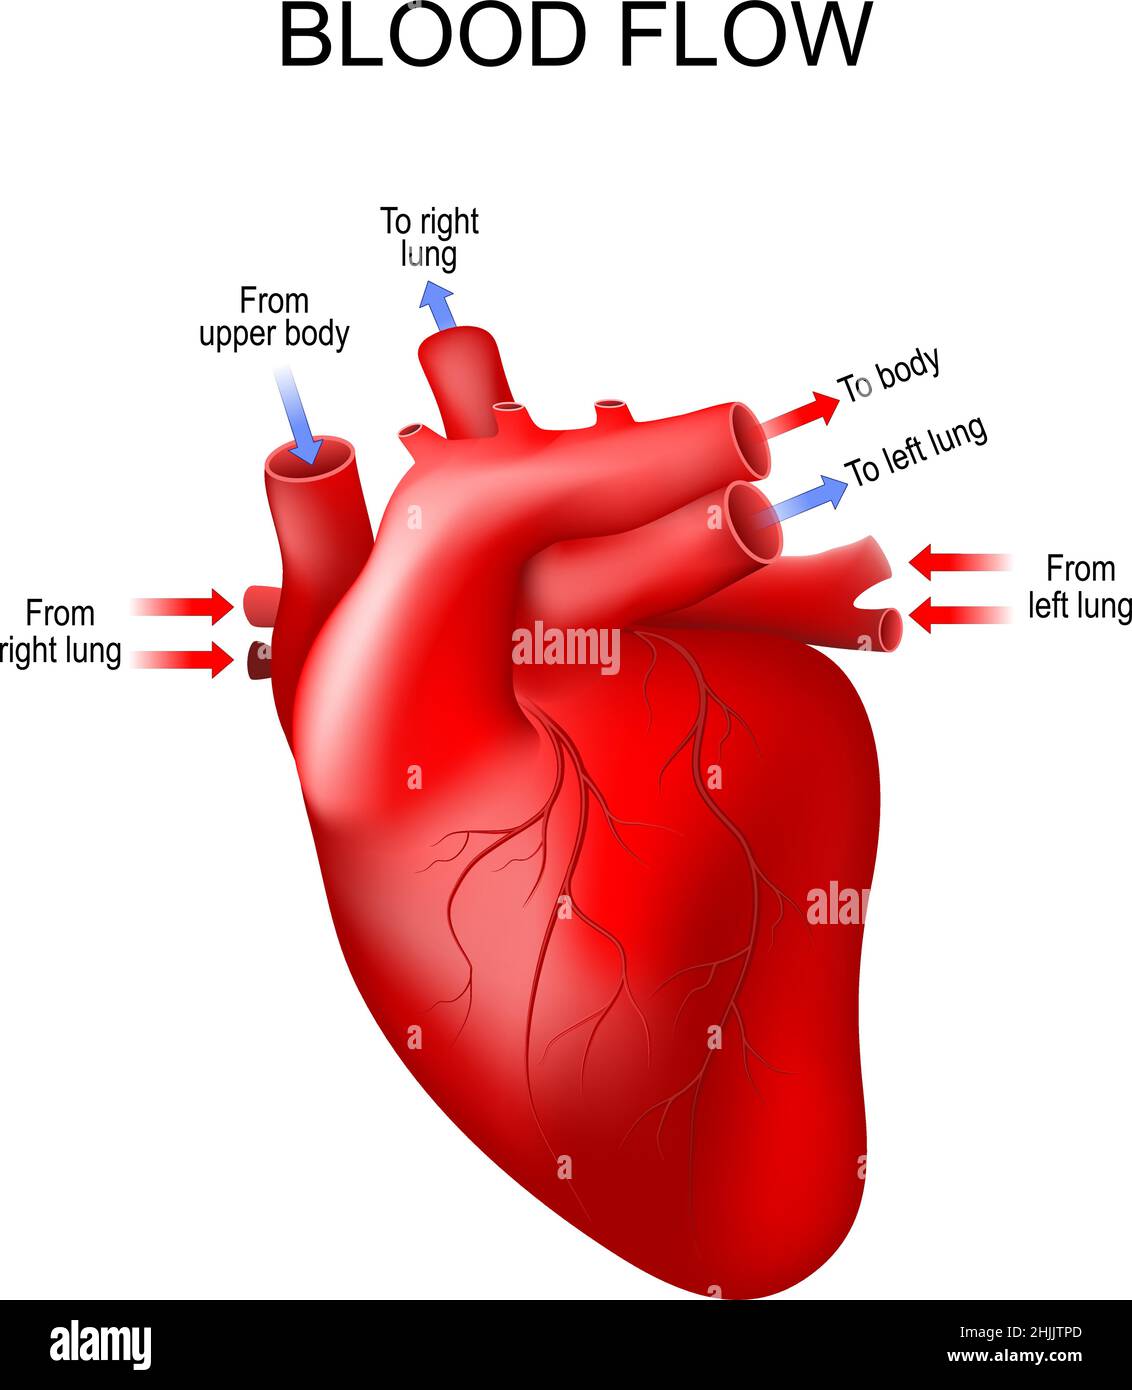

human heart anatomy. arrows show the normal direction of blood flow. Vector poster Stock Vectorhttps://www.alamy.com/image-license-details/?v=1https://www.alamy.com/human-heart-anatomy-arrows-show-the-normal-direction-of-blood-flow-vector-poster-image458947957.html

human heart anatomy. arrows show the normal direction of blood flow. Vector poster Stock Vectorhttps://www.alamy.com/image-license-details/?v=1https://www.alamy.com/human-heart-anatomy-arrows-show-the-normal-direction-of-blood-flow-vector-poster-image458947957.htmlRF2HJJTPD–human heart anatomy. arrows show the normal direction of blood flow. Vector poster